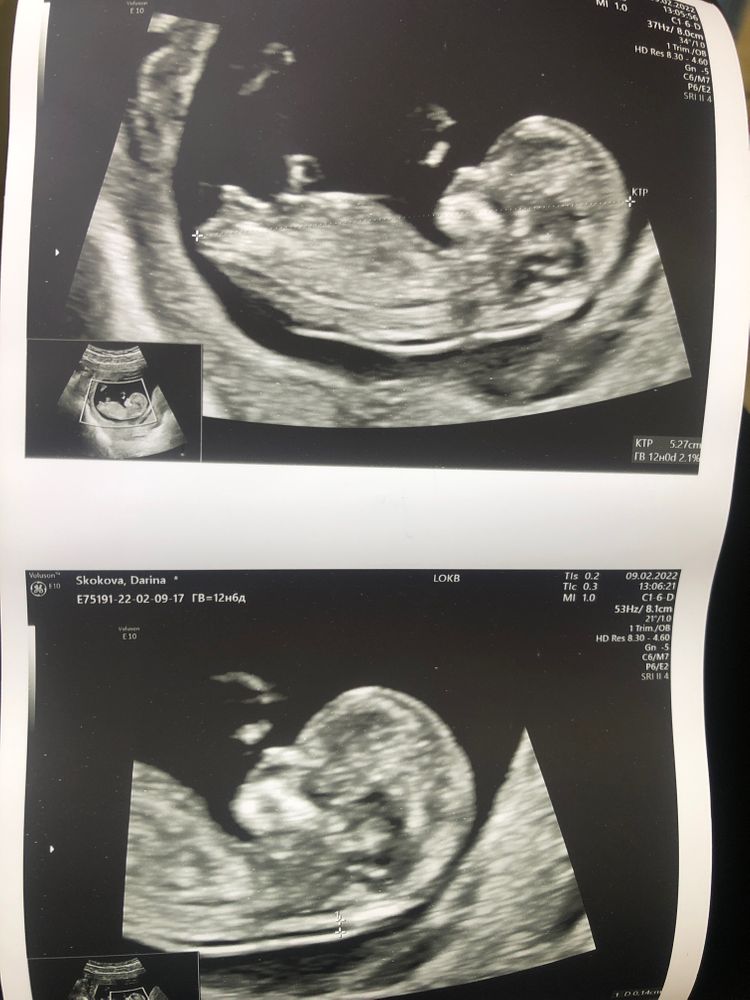

Пол ребёнка.

Девочки, была на скрининге. Срок оказался чуть меньше и врач сказала, что на сроке 11,4 половых признаков нет совсем. Ничего не сформировано ещё и даже не собирается пока формироваться. Неужели Действительно это так? А как же другим предполагают пол и на .10,5 неделе? Ничего не понимаю.

Узист права- половые органы формируются позже . На вашем сроке пол определяют по направлению полового бугорка.

на вашем снимке похоже девочка.

Но, судя по Вашему снимку и направлению бугорка- у Вас девчуля

По наклону полового бугорка на девочку похоже. А вообще, мне пол на 1 скрининге тоже не говорили. На 2 скрининге сказали точно, в 19 недель.